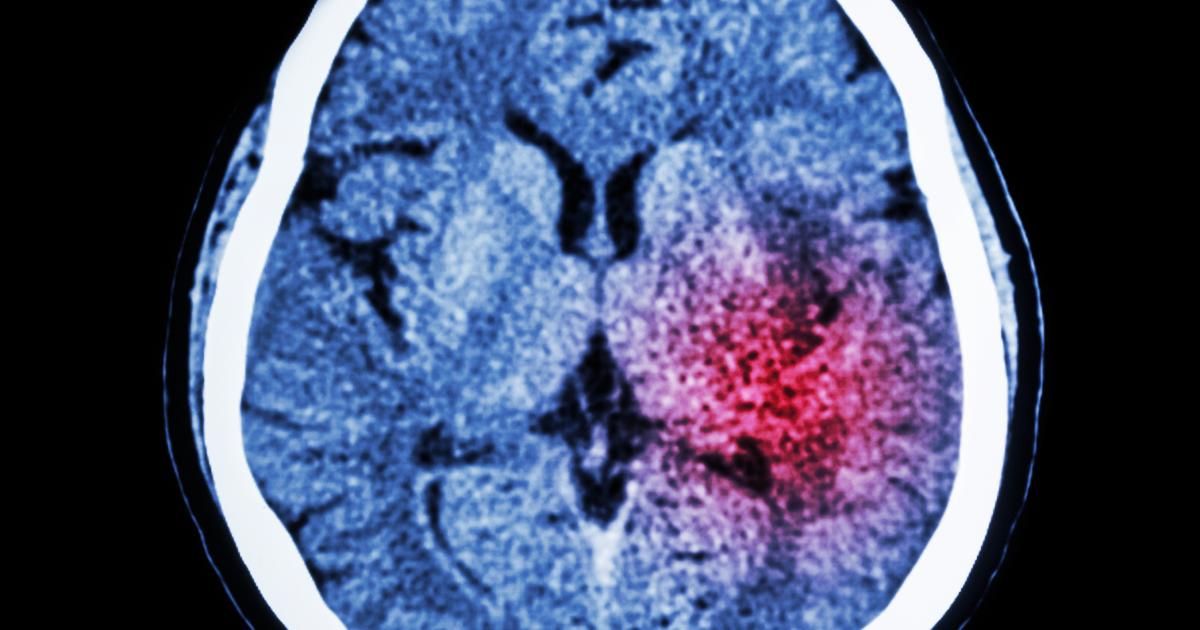

Recovering from brain injury Dr Scott Ramsay, Consultant Physician in Medicine for the Elderly and Stroke Medicine, NHS Lothian IMT curriculum Clinical Capabilities in Practice: * Managing a multidisciplinary team including effective discharge planning * Managing patients in an outpatient clinic, ambulatory or community setting (including management of long term conditions) * Providing continuity of care to medical patients, including management of comorbidities and cognitive impairment IMT curriculum presentations and conditions: Stroke * Weakness and paralysis * Unsteadiness * Speech disturbance * Swallowing difficulties |

Updates in hyperacute stroke Dr Matt Lambert, Consultant Physician in Medicine for the Elderly and Stroke Medicine, NHS Tayside IMT curriculum Clinical Capabilities in Practice: Delivering effective resuscitation and managing the acutely deteriorating patient * Managing an acute unselected take * Managing the acute care of patients within a medical specialty service IMT curriculum presentations and conditions: Stroke * Weakness and paralysis * Unsteadiness * Speech disturbance * Swallowing difficulties |